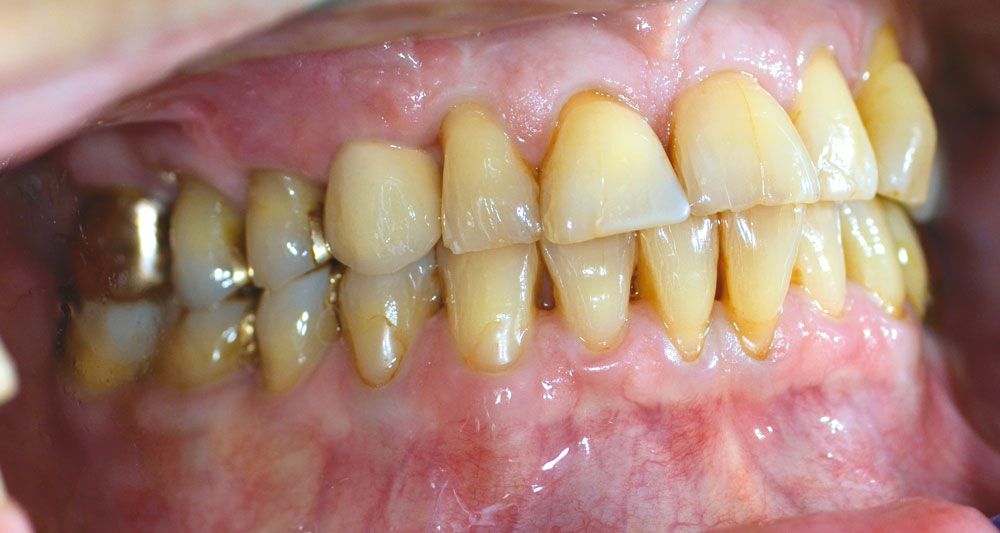

01/12 - Initial situation - bone defect in maxilla after loosing right canine

Block augmentation with maxgraft® in the maxilla - PD Dr. Dr. F. Kloss